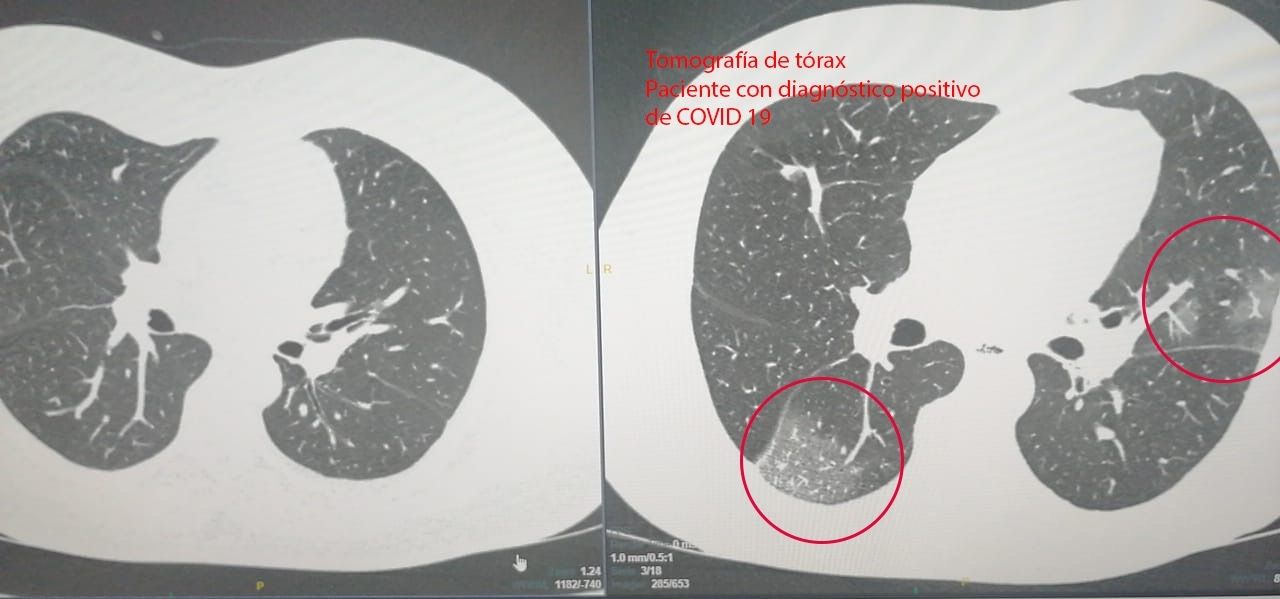

Pero, fundamentalmente permite estadificar el compromiso pulmonar frente a Covid-19 por el tipo de lesiones que provoca y diagnósticos múltiples diferenciales con otras enfermedades respiratorias, colocando a la Tomografía de tórax en un estudio vital ya que a través de él se aventaja incluso el cuadro clínico (fiebre, tos, etc.), ganando así tiempo vital para el paciente.

"La estadificación que se logra mediante el estudio de TC de tórax, se divide en leve, moderado o severo, lo que es fundamental para el tratamiento más adecuado teniendo en cuenta lo agresivo que es el virus potenciándose incluso en pacientes de riesgo", explicaron desde la Fuesmen.